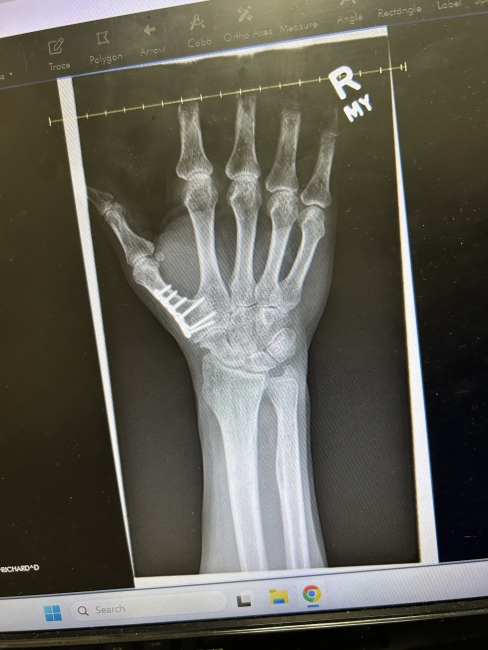

Fusion and arthritis removal CMC JOINTS left and right hands.

Resuming Ironworking & Race Car Driving

I couldn’t even hold a cup of coffee, my hands hurt so bad. Dr. McBride did a wonderful job on both my thumbs. I have six screws and plates in each thumb. Yes, I have a little arthritis coming…